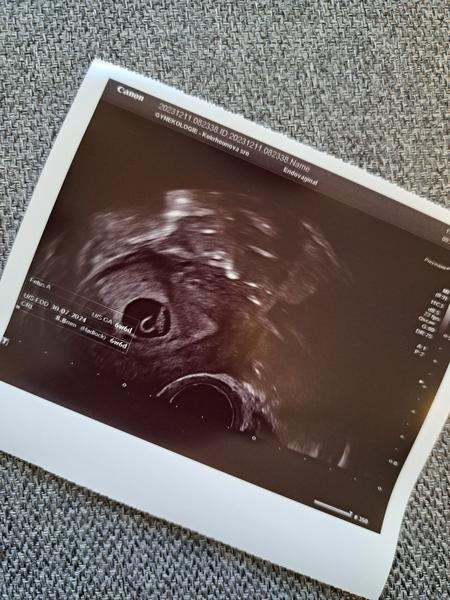

Ahoj, také jsem to měla stejně jako ty, na ultrazvuku nic, testy pozitivní i o mimoděložním u mě doktor tvrdil že je nepravděpodobné, v krvi mi hcg hezky rostlo a teďka už jsem 21tt, vůbec bych se nestresovala, taky jsem se tu ptala a bála se jestli je všechno v pořádku, nakonec to dopadlo dobře 🙂😊 přikládám fotku z 6+6tt, on se určitě brzy ukáže, držím palce 😊